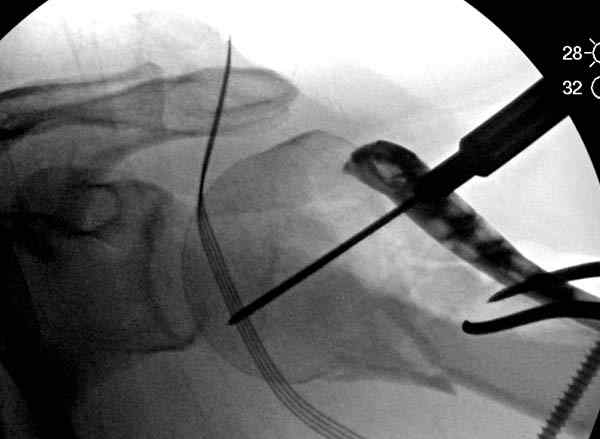

Для облегчения рентгенологического контроля во время операции мы применяем полусидячее, так называемое положение “beach chair” на операционном столе. Наши столы позволяют поднять ножной конец до необходимой высоты, только надо усадить больного к ножному концу стола.

Ошибки встречаются тогда, когда удовлетворяются только одной проекцией рентгена.

Здесь пример открытой репозиции 57 летнего с переломом плеча (1,2) смещение обнаружено на интероперационном снимке. При нормальной прямой проекция (3) угловое смещение обнаружили в аксиальной проекции (4)